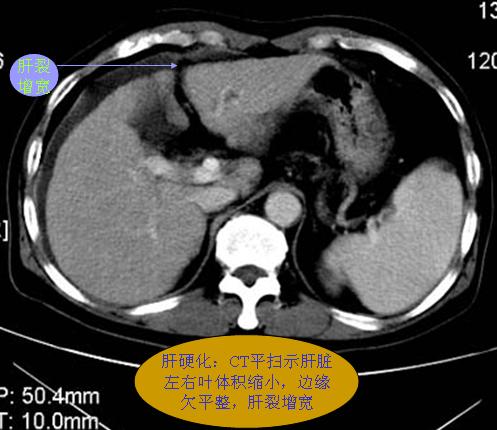

腹部ct解剖与基本病变